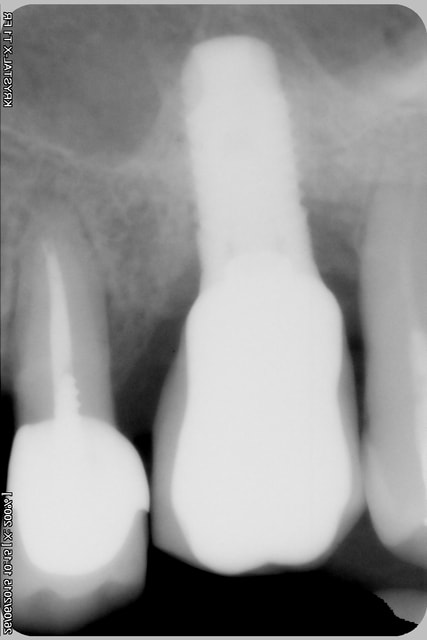

une radio d'implant, pas terrible mais peut être suffisante pour toi Pluton?

Pour le reste, pas génial, j'attends le scanner pour décider de la suite.

> une radio d'implant, pas terrible mais peut être suffisante pour toi Pluton?

pas terrible en effet....

mais bon, il a quand même une bonne tête de SERF EVL N....

heu...les pièces prothétiques c'est chez Global D maintenant...;-)